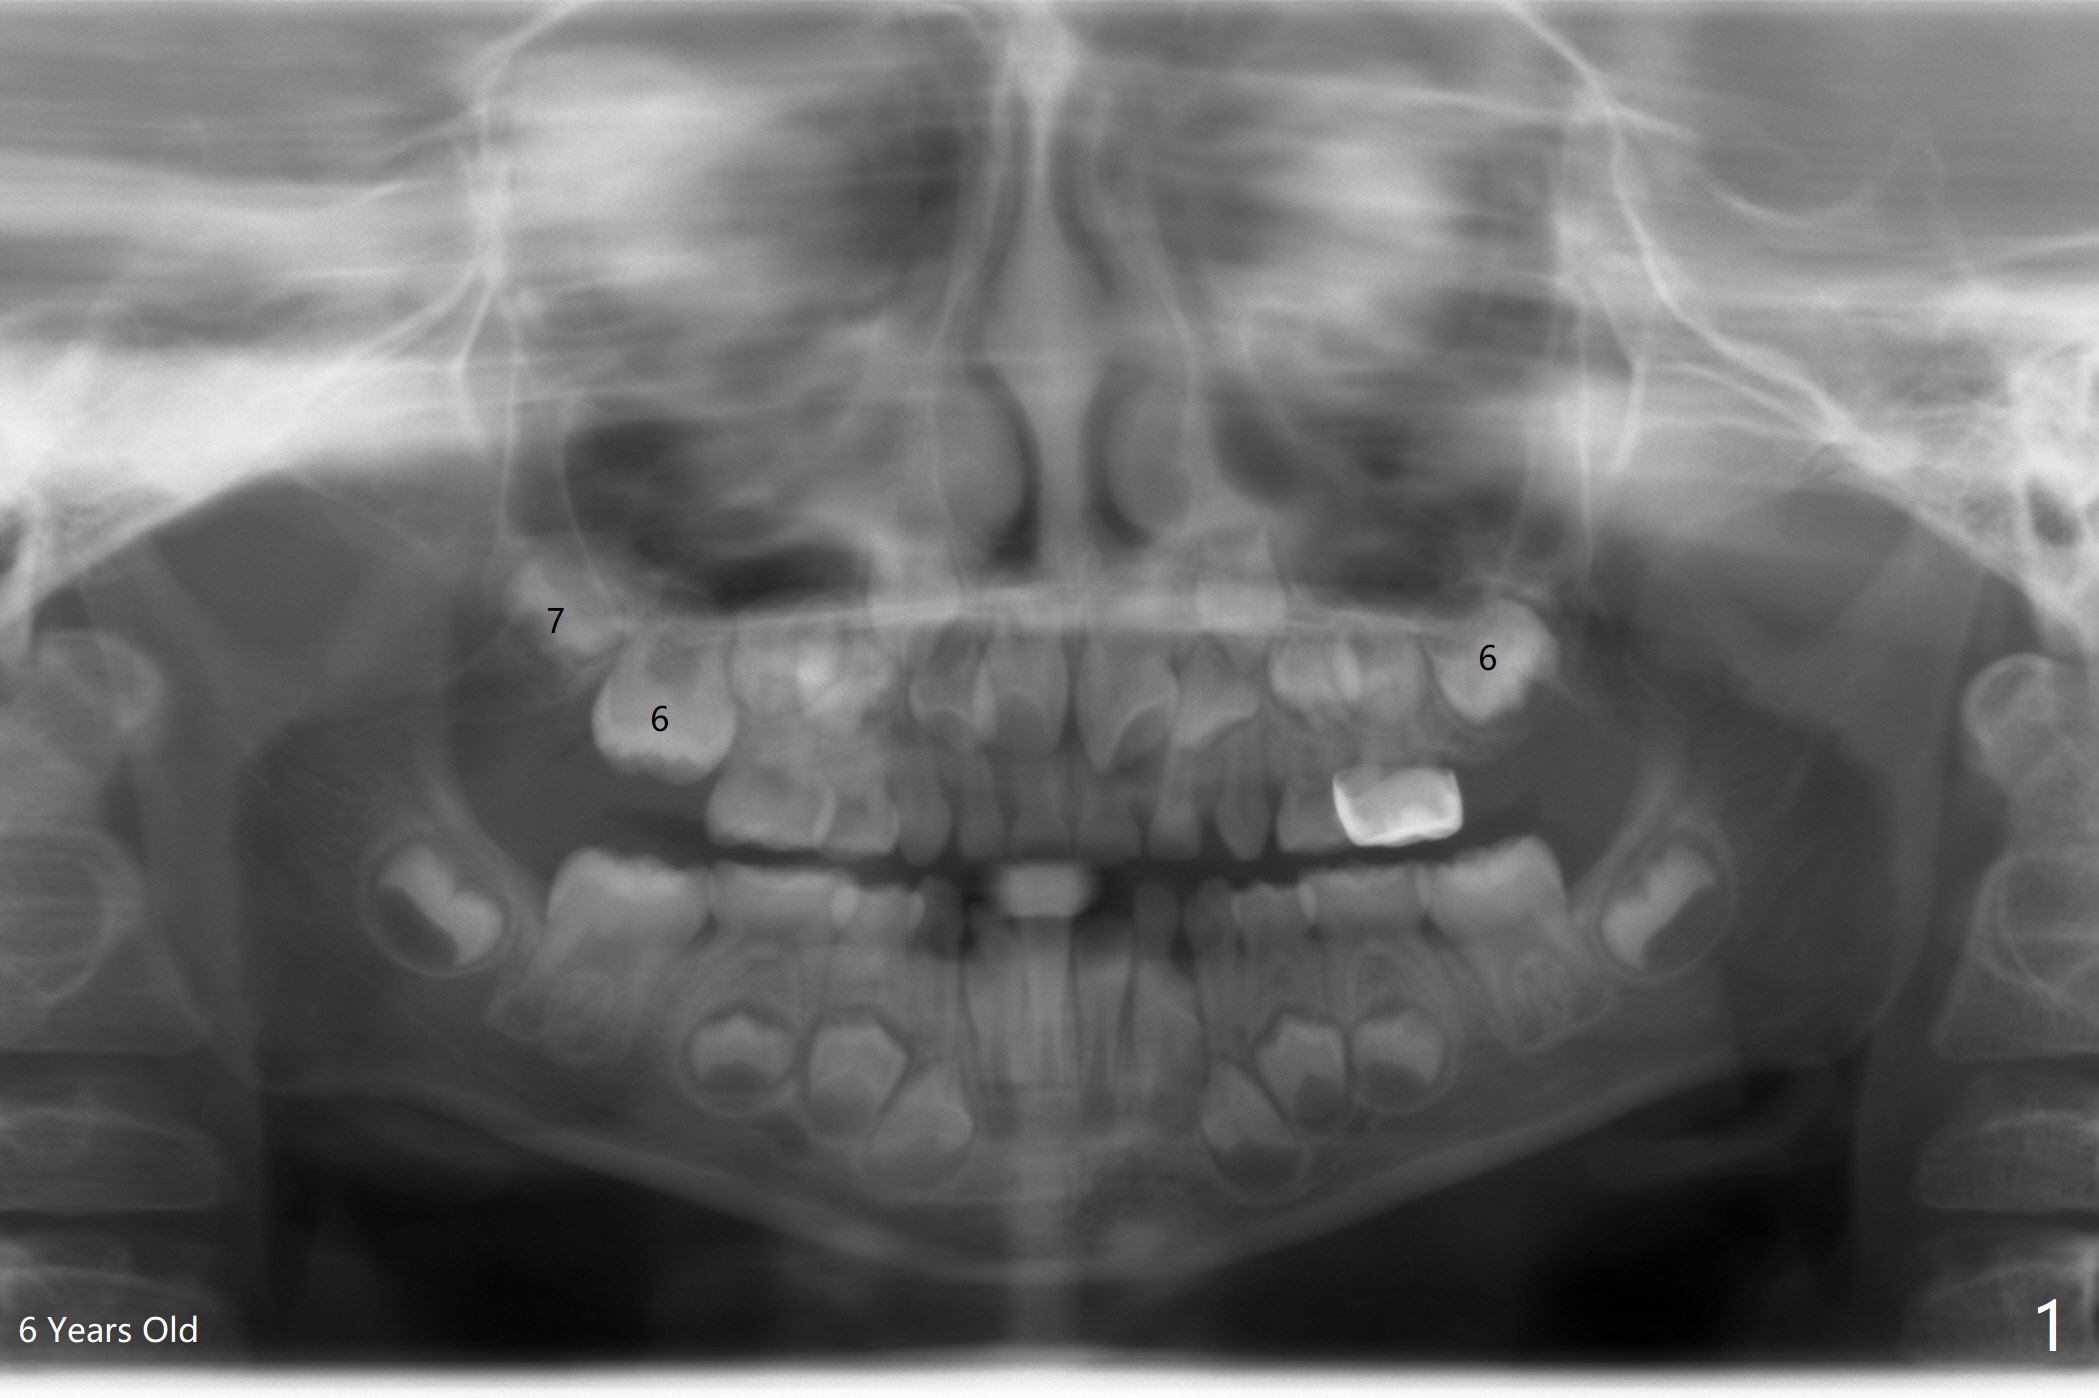

The upper left 1st permanent molar of a female remains unerupted between the age of 6 and 8 years old (Fig.1-4). The distal root of E is resorbed (Fig.3), which may be a reason of blockage. It appears that the upper left molars are underdeveloped, including 7. Or UL6 is congenitally missing? What is the treatment plan? Wait or surgery?